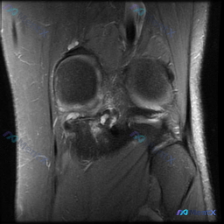

最近碰到一个有意思的病例,患者主诉考虑膝关节软骨异常,只提供了一张髌股关节层面的T1加权轴位MRI,整理一下分析思路和大家讨论。 病例基本信息 - 核心问题:评估影像是否存在软骨异常 - 影像资料:单张膝关节髌股关节层面T1加权轴位MRI 影像读片结果 先给大家整理读片的核心发现: 1. 骨骼结构:...